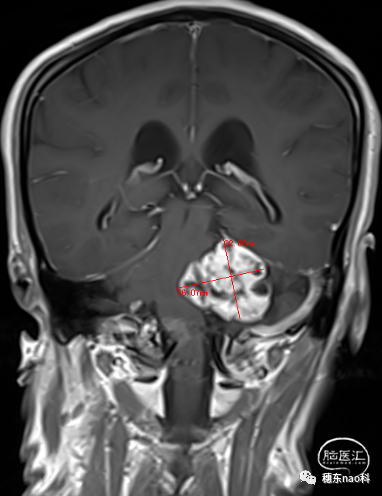

头颅MRI:

左侧桥小脑区占位,最大长径约4cm*3cm